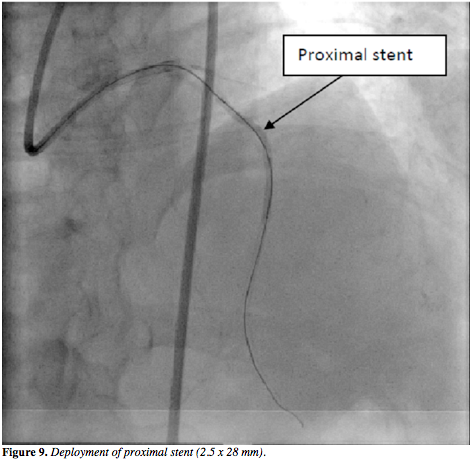

was then advanced through the subintimal dissection into the proximal LAD (Figure 6) and then the Corsair was advanced over this wire proximal to the CTO segment. As a result, the true lumen of the distal LAD was then successfully negotiated with a Fielder XT guidewire in an antegrade fashion (Figure 7). The retrograde wire with Corsair was removed. After successful balloon dilatation, two Yukon stents (Translumina) of 2.5 x 32 mm and 2.5 x 28 mm were deployed (Figures 8 and 9), with an optimal angiographic result (Figure 10 and Video 2). The patient is free of symptoms after 6 months of follow-up.